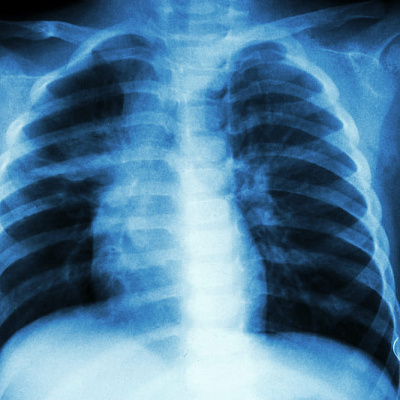

- рентгенологическое исследование, которое позволяет распознать заболевание, оценить его особенности (а также конкретное место, пораженный отдел).

При необходимости проводятся КТ, МРТ легочных структур, если остаются сомнения в правильности диагноза.